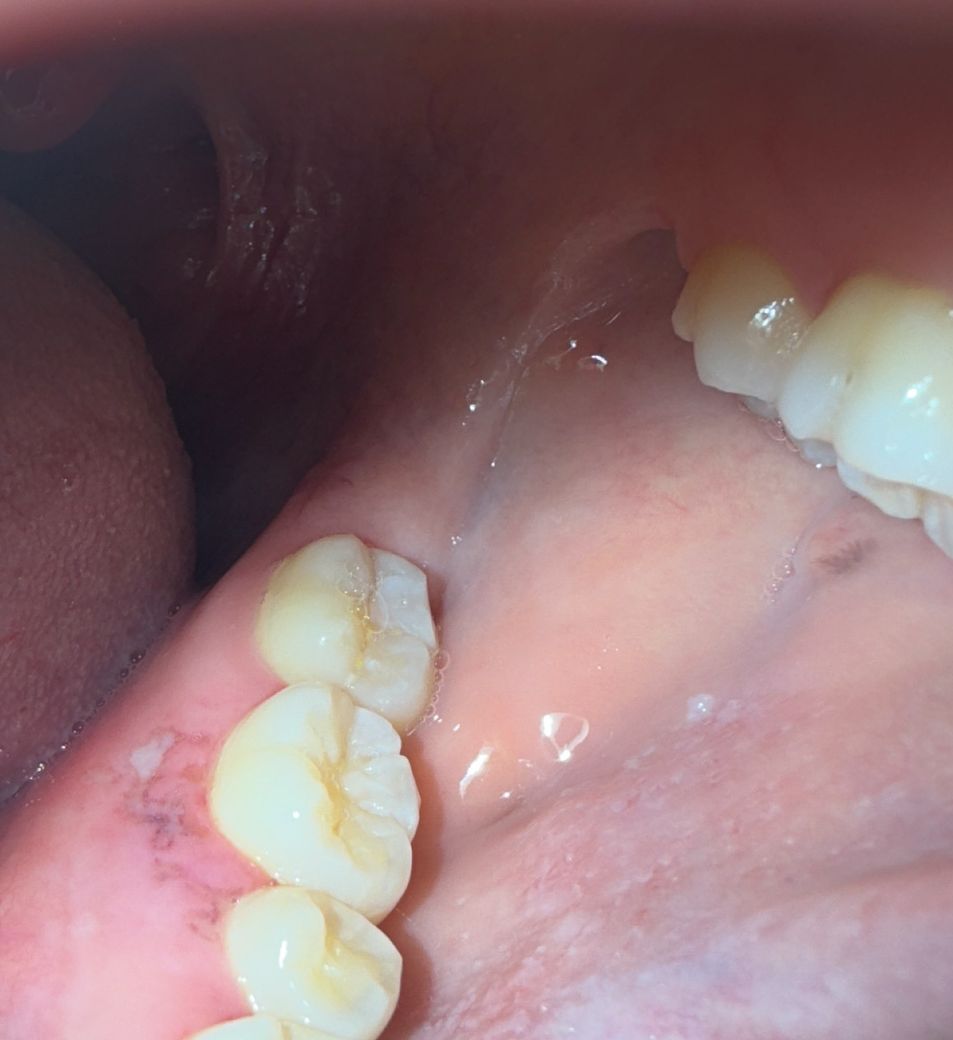

사진은 순서대로 목요일 - 금요일(어제) - 금일오전 - 금일 오후입니다. 처음엔 부어서 살이 울퉁불퉁 올라온 느낌(통증없음), 살짝 하얗게 수포처럼 올라옴 (통증 무), 염증 아문 듯한 빨간 흉터 (통증무), 오늘은 마치 긁힌? 패인? 듯한 염증자국 (혀로 건들면 정말 아주 조금 따끔)

혀로 만져보면 오늘은 실제로도 패인듯한 촉감입니다 ㅜ 네번째 사진에 허옇게 보이는 건 팝콘찌꺼기 일수도 있어요 (방금 먹고 찍었는데 억지로 빼긴 아파서 그대로 찍었어요ㅠ)

• 1번 째 사진